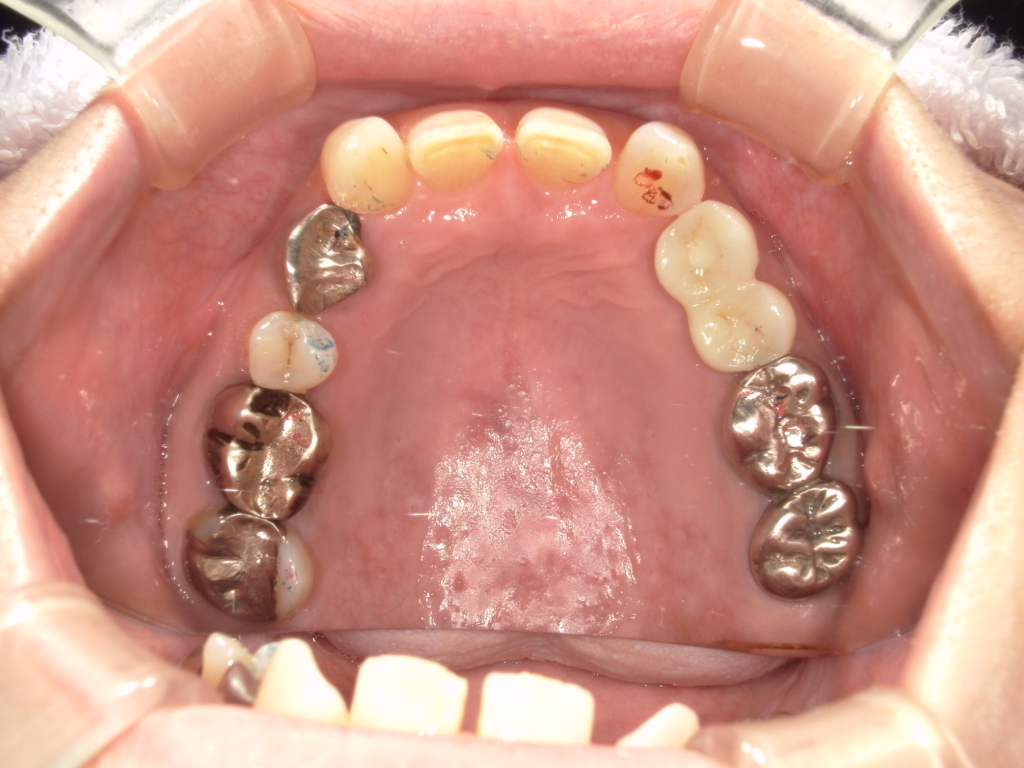

Y様インプラント実例 #44

左の上下の奥歯をインプラントで治療しています。

左下の奥歯は歯を抜くのと同時にインプラントの埋め込みを行っています。

被せものは上下、セラミックスで作っています。

治療前

治療後